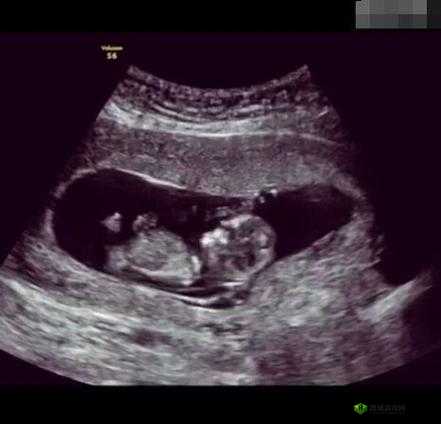

当我们躺在 B 超室的床上,医生突然问“这是第几胎”时,可能很多人都会心生疑惑,这到底是在暗示什么呢?其实,这背后可能有以下这 5 个原因。